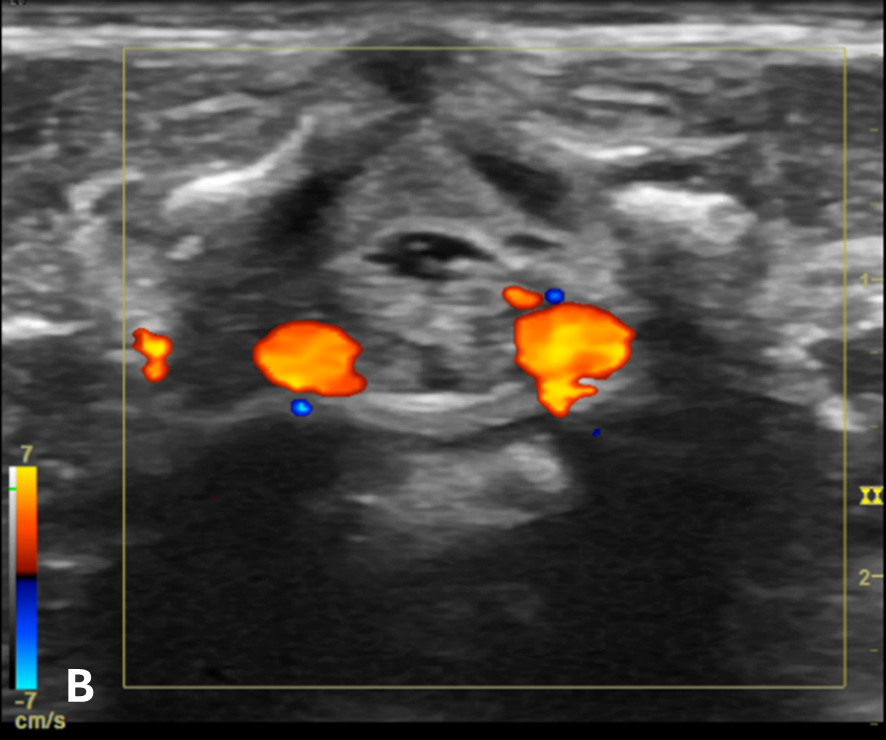

The transverse view should also be obtained to verify landmarks and identify any overlying vessels or hematomas (from prior attempts) to avoid. The transducer is rotated to the transverse position on the lower back and moved caudally over the spinous processes to locate the CM, which is a hypoechoic structure positioned in the center of the spinal canal. At higher levels of the CM, the ventral roots and dorsal roots can be identified, which are surrounded by the anechoic CSF. Next, gradually move the transducer caudally and observe the CM decreasing in size while being encircled by the hyperechoic fibers of the CE. (Figure 2) Once this sonographic landmark is identified, locate the center of the transducer and mark the corresponding area on the skin, aligning it with the center of the spinal cord. Subsequently, draw lines from both markers in both planes and utilize the point of intersection as a guide for inserting the LP needle. To enhance visualization of the spinal cord’s vascular supply, and avoid a space with any overlying vessels that may cause a traumatic tap, it is advisable to apply color Doppler in both the sagittal/longitudinal and transverse views.9 (Figure 3)

Figure 3 - Color Doppler US image of the spinal canal:

Figure 3B - The transverse view shows the anterior spinal blood vessels at the lateroventral part of the spinal canal.